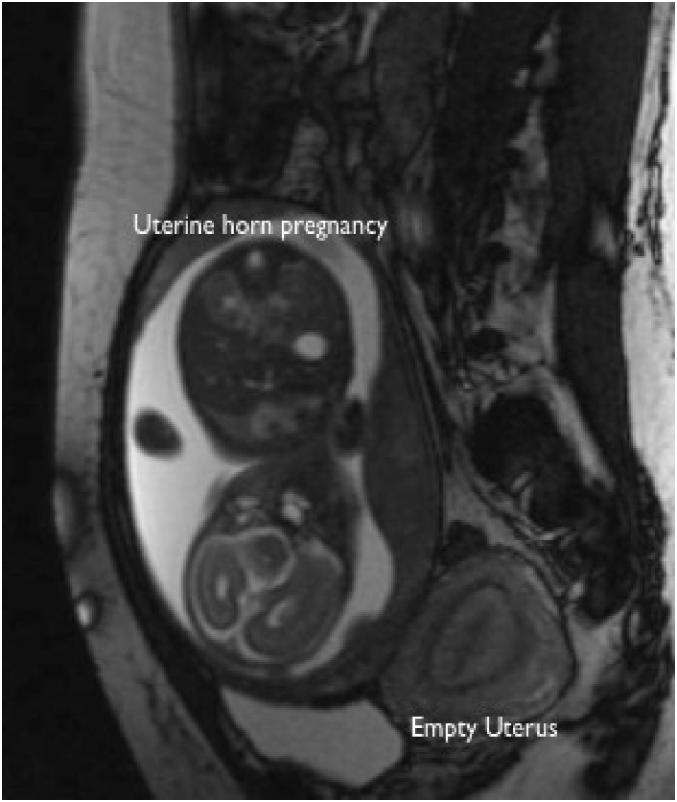

Periviable delivery of a pregnancy in a rudimentary uterine horn: A case report.

Pregnancy in a rudimentary uterine horn is an extremely rare form of ectopic pregnancy, with an incidence of 1 in 76,000-140,000 pregnancies. Given its high-risk nature, the standard of care is to terminate such pregnancies at the time of diagnosis. This is a case of a nulliparous patient at 23 5/7 weeks of gestation with a new diagnosis of a rudimentary horn pregnancy. She elected to proceed with full intervention for her fetus and was delivered at 24 0/7 weeks after administration of antenatal corticosteroid therapy. While the infant did have some adverse effects related to prematurity, she met developmental milestones and was alive and well at the age of two. Although the standard of care is to manage these cases as ectopic pregnancies, when diagnosed at a periviable gestational age, optimization of fetal status prior to delivery may be an alternative approach to immediate delivery.